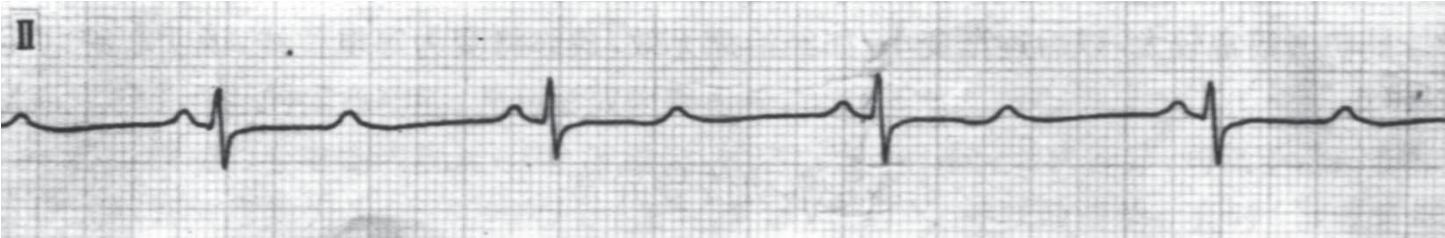

1.窦性心动过速 成人窦性心律的频率超过100次/分,称为窦性心动过速。心电图表现:成人频率大多在100~150次/分(图3-4)。

图3-4 窦性心动过速